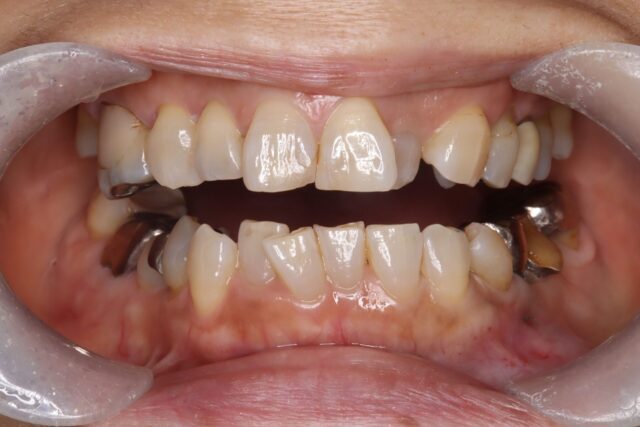

術前口腔内

叢生状態を認める

また不適切な被せ物が多数認められる